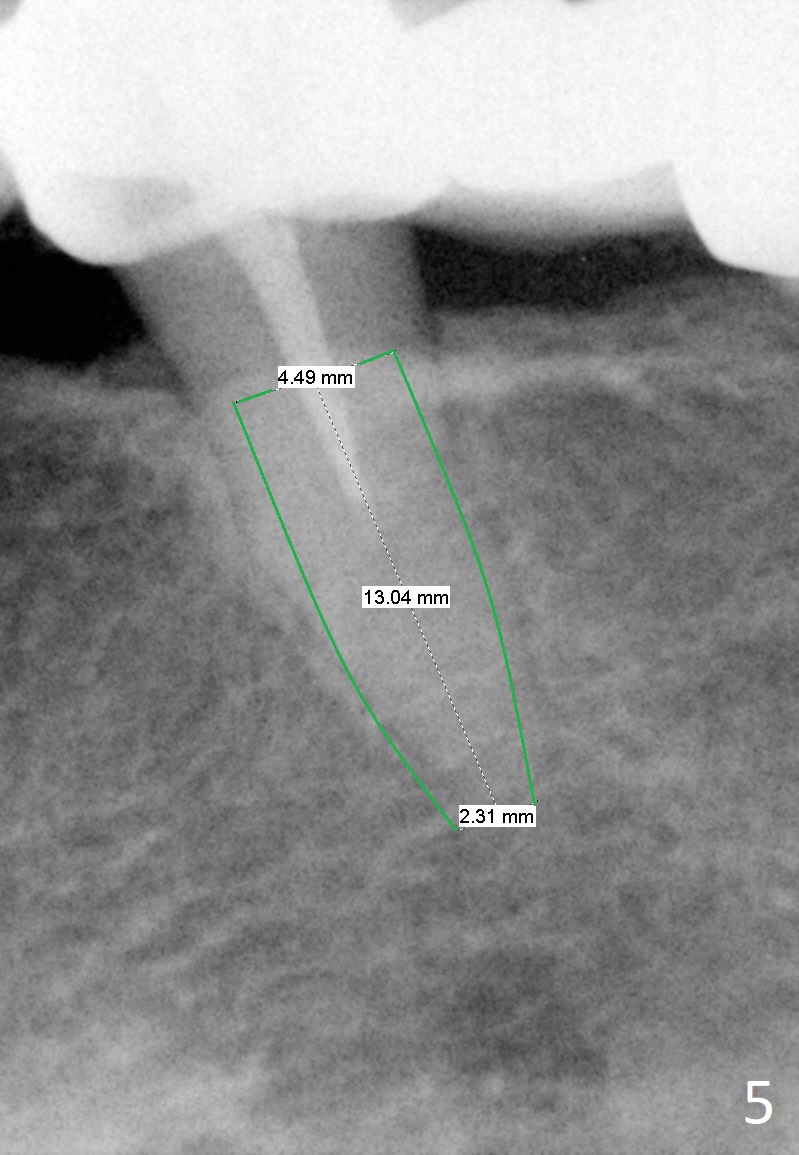

A 65-year-old woman used to have a long bridge (Fig.1). First, the portion mesial to #20 was sectioned. But the remaining portion kept chipping. RCT was retreated for the tooth #20 as the first step to have separate crowns at #18 and 20 and have a lower partial redo. Instead a new FPD was done between #18 and 20 in her own country (Fig.2). Two years later, the tooth #20 became symptomatic with increased pdl mesially (Fig.3*). Periradicular radiolucency increases in another 2 years (Fig.4). The apex of the affected tooth (yellow dashed line) is close to the Mental Loop (red dashed line, Fig.1-3). Although the loop is buccal to the apex of the 2nd premolar, an implant will not extend past the apex to avoid neuropathy (Fig.5). No Inferior Alveolar Nerve block will be administered. PA will be taken after pilot drill. The FPD will be sectioned between #18 and 19. To compensate for the short length of the implant, try to place a large one as long as the buccolingual bone allows. Adapt the lower RPD to the immediate provisional, which should be as small as possible, since the retention must be not too high.